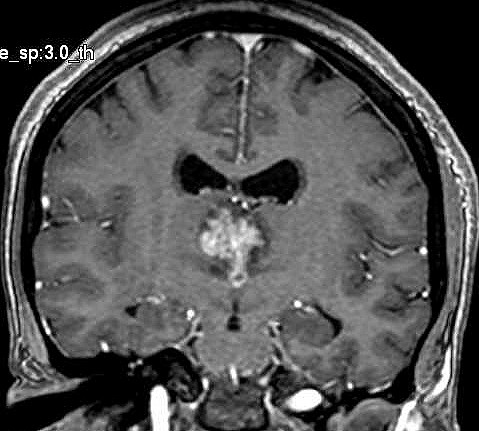

| Fem. 17a. |

| Nódulo sólido homogêneo preenchendo o III ventrículo, com limites precisos, com hipossinal em T1 e hipersinal em T2 e FLAIR, que se impregna por contraste paramagnético. Lesão menor implantada no assoalho do IV ventrículo provavelmente representa disseminação por via liquórica. |

| F. 17a. Tumor teratóide rabdóide atípico de III ventrículo. RM | HE | VIM, GFAP | HHF35, desmina, 1A4 | AE1AE3, EMA |